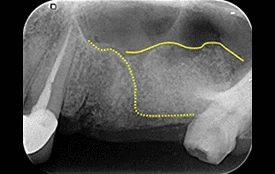

7. 上顎竇增高術

上顎竇位於上顎後牙區的正上方,是副鼻竇的一種,基本上是個充滿氣體的腔室,牙齒拔除後,上顎竇可能往下延伸到無牙區,造成缺牙區齒槽骨的不足。

本院利用專利器械將上顎竇膜提高並降低黏膜穿孔破裂的機率及避免術後感染(有時會合併骨粉)的使用,以利人工植體植入。

↑ 治療後:微創補骨增高鼻竇,不腫脹

↑ 手術後二周傷口完全癒合